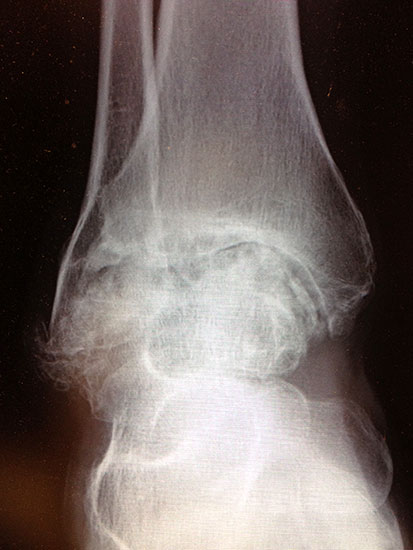

Kapsulotomie und Synovialektomie. Entknorpeln der Gelenkflächen bis knapp in den subchondralen Raum. Mit Kuretten, gebogenem Meißel, oszillierender Säge und/oder hochtourigen Fräsen Entknorpeln der tibialen, fibularen und tibialen Gelenkfläche und Abtragung von knöchernen Anbauten (Abb. 3). Die Präparation entlang der vorgegebenen Kontur des Talus und der Tibia bietet den Vorteil eines geringeren Längenverlustes gegenüber geraden Sägeschnitten. Der anteriore Zugang bietet insbesondere bei Verwendung eines Arthrodese Spreizers eine gute Übersicht in die anterioren Kompartimente. Der antero-laterale transfibuläre Zugang ergibt eine hervorragende Übersicht, allerdings nicht auf das mediale tibio-talare Kompatiment.

Abbildung 3